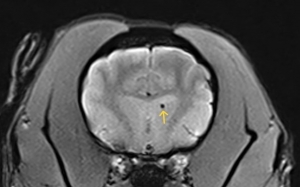

✎ 圖二為13歲狗狗出現腦部血腫,為出血性中風。

- MRI 是診斷黃金工具:能清楚觀察缺血/出血位置與範圍,一些特殊序列如加權梯度回波序列(T2*W、GRE)、擴散加權成像(DWI)等對出血及缺血性病灶極具診斷力